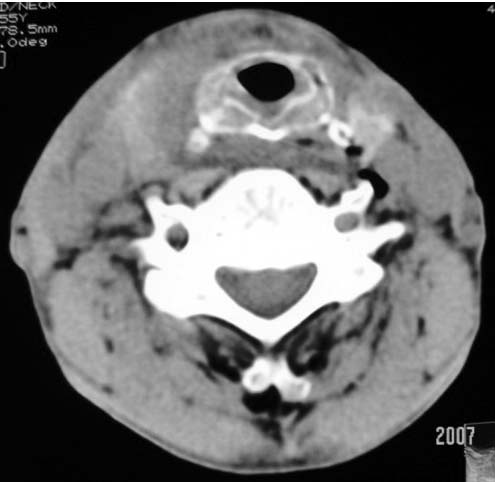

以下是引用dyqct在2007-4-20 16:19:00的发言:[br]考虑:1、左侧梨状窝区破裂伴左颈深、浅部气肿。[br] 2、右侧甲状腺区血肿(请追问病史是否伤及右颈部)。[br] 3、建议病情稳定后增强扫描除外右侧甲状腺腺瘤。